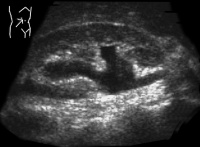

Harnwegsinfekte: Was macht der Urologe und wann sollte er eingeschaltet werden?

Journal für Urologie und Urogynäkologie 2011; 18 (1) (Ausgabe für Schweiz): 32-34 Journal für Urologie und Urogynäkologie 2011; 18 (1) (Ausgabe für Österreich): 31-32 Volltext (PDF) Abbildungen